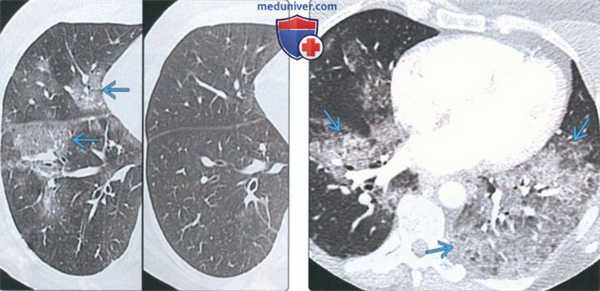

(Слева) На корональной КТ без КУ (MIP) у мужчины 31 года с аллергическим бронхолегочным аспергиллезом и периферической эозинофилией определяются двухсторонние бронхоэктазы со слизистыми пробками в просвете. Некоторые из этих пробок имеют характерный вид «пальцев в перчатке».

(Справа) На корональной КТ без КУ у этого же пациента в язычковых сегментах левого легкого визуализируется гиперденсная слизистая пробка. Слизистые пробки обнаруживаются у 30% пациентов с аллергическим бронхолегочным аспергиллезом.

• АБЛА:

о Центральные бронхоэктазы, более выраженные в верхних долях:

- Слизистые пробки высокой плотности (30%)

- Ателектаз или спадение легкого дистальнее зоны обструкции бронха